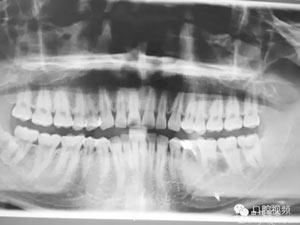

圖1.術(shù)前的全景片影像檢查,35移位至36、37之間。

圖15.術(shù)后的全景片資料